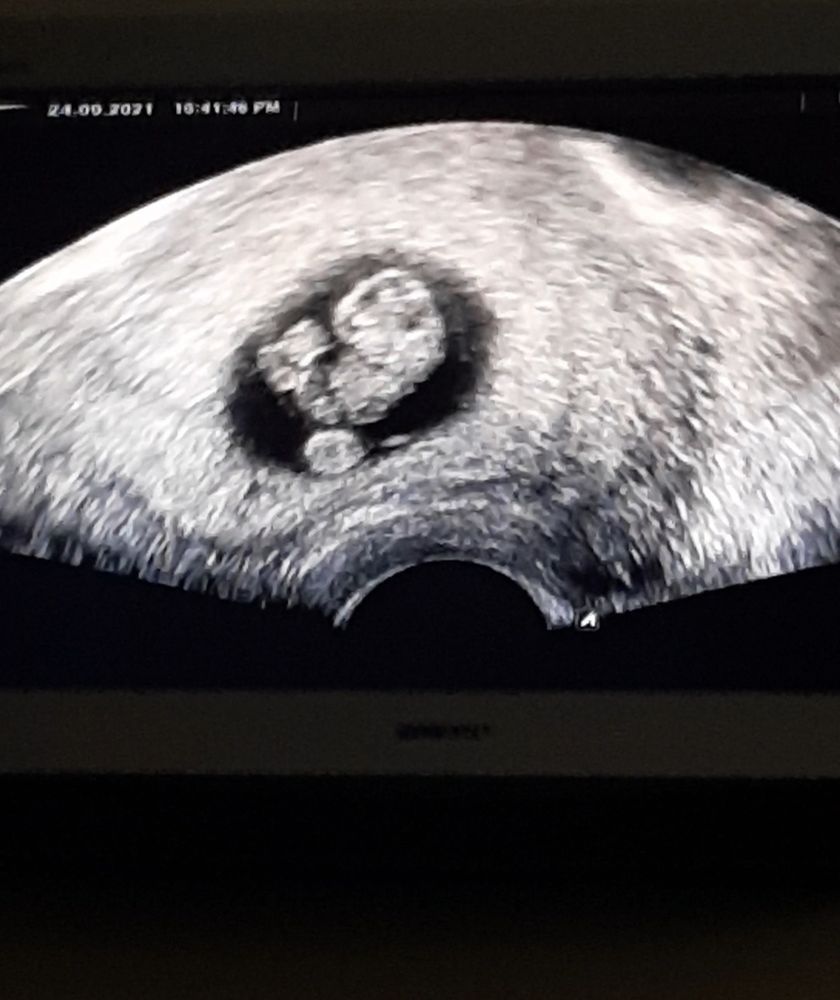

Это же пуповина?

Пуповинка)

Мила, вот я не знаю как оно должно быть. Двойня это же разные ПЯ? А тут какбы в одном, то есть близнецы? Это максимально неожиданно 😅 но я все таки думаю что пуповина так намоталась, но может девочки з близнецамм подскажут, опыта то больше.

Мила, да, там была масенькая точка бела и круглый жмя. Плодное яйцо четко было видно в матке, без сомнений. Но это точно не двойня. Либо близнецы либо все таки пуповина такая шальная 😅 я тоже тут читала сколько что и с первого раза фиг получиться, и нужно тесты мочить послк задержки и то не факт что увидишь, и на узи первое в 7-8 недель топать. А у нас первый цикл и все куда нужно, токсикоз на 10 дпо и вот как прилетели с отпуска, сделада тесты и реально охренела. Беременная полоска быстрее вылезла чем тестовая. Вообщем все не так как у всех 😅